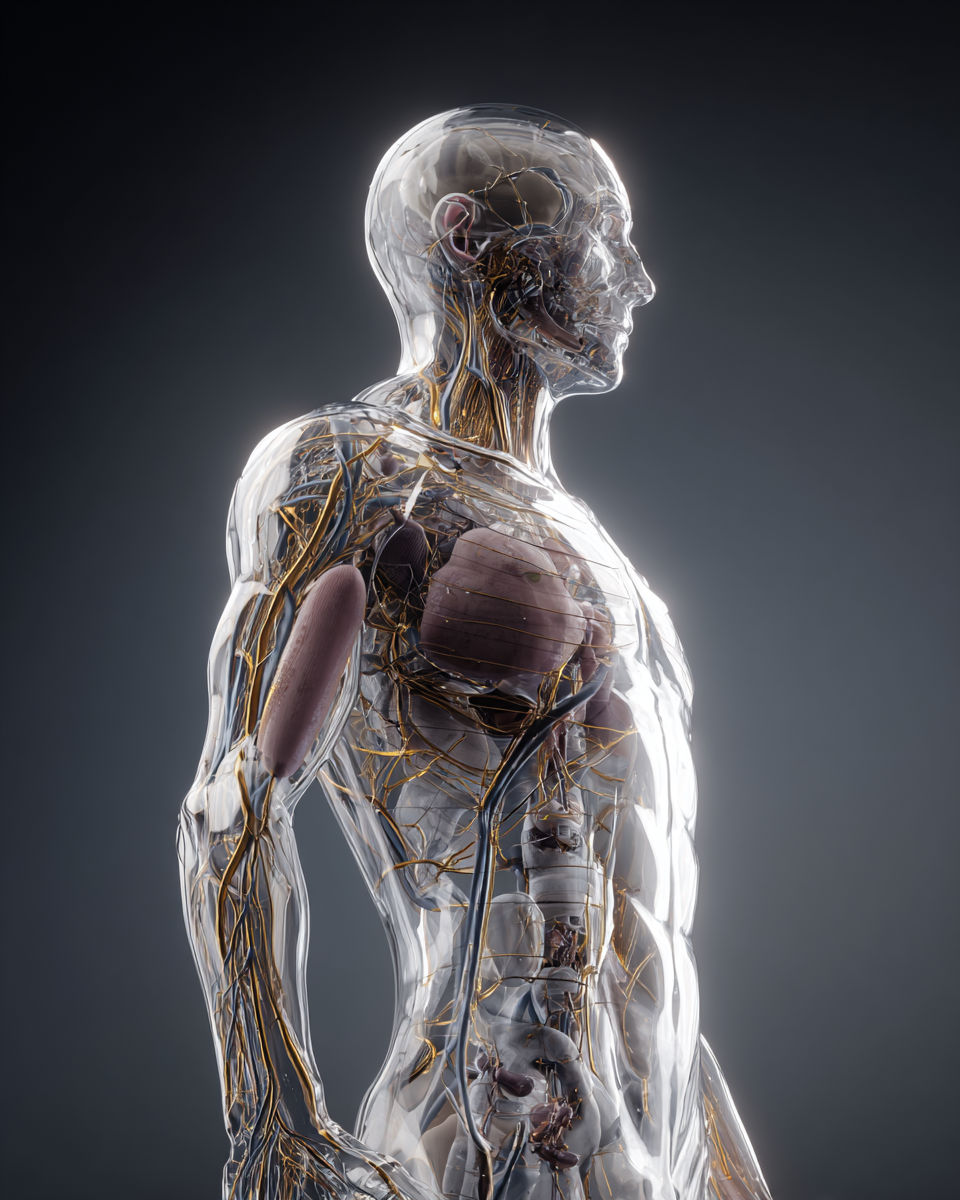

Los péptidos son señales biológicas capaces de activar procesos naturales del cuerpo como regeneración, equilibrio y bienestar.

Los péptidos son pequeñas cadenas de aminoácidos que el propio cuerpo produce de forma natural y que actúan como mensajeros biológicos, participando en distintos procesos del organismo.

Desde un enfoque de bienestar, los péptidos pueden apoyar procesos naturales del cuerpo relacionados con:

Comunicación celular

Equilibrio metabólico

Regeneración y reparación

Energía y bienestar general